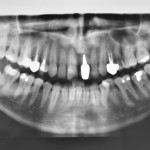

Autotrapianto di ottavo incluso a sostituzione di un settimo irrimediabilmente compromesso: case report

Riassunto

I trapianti dentali sono un capitolo...